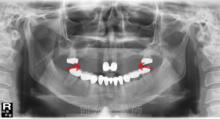

5.恆牙列中任何一顆牙都有先天缺失的可能,最常見為第三磨牙,其次為下頜第二前磨牙、6.上頜側切牙和上頜第二前磨牙。最少缺失的是第一磨牙,其次是第二磨牙。

7.缺磨牙的患者多伴有其他牙齒的缺失,單純缺磨牙者少。

8.牙齒缺失可發生在單側也可發生在雙側。

9.缺失牙位多呈對稱性分布。